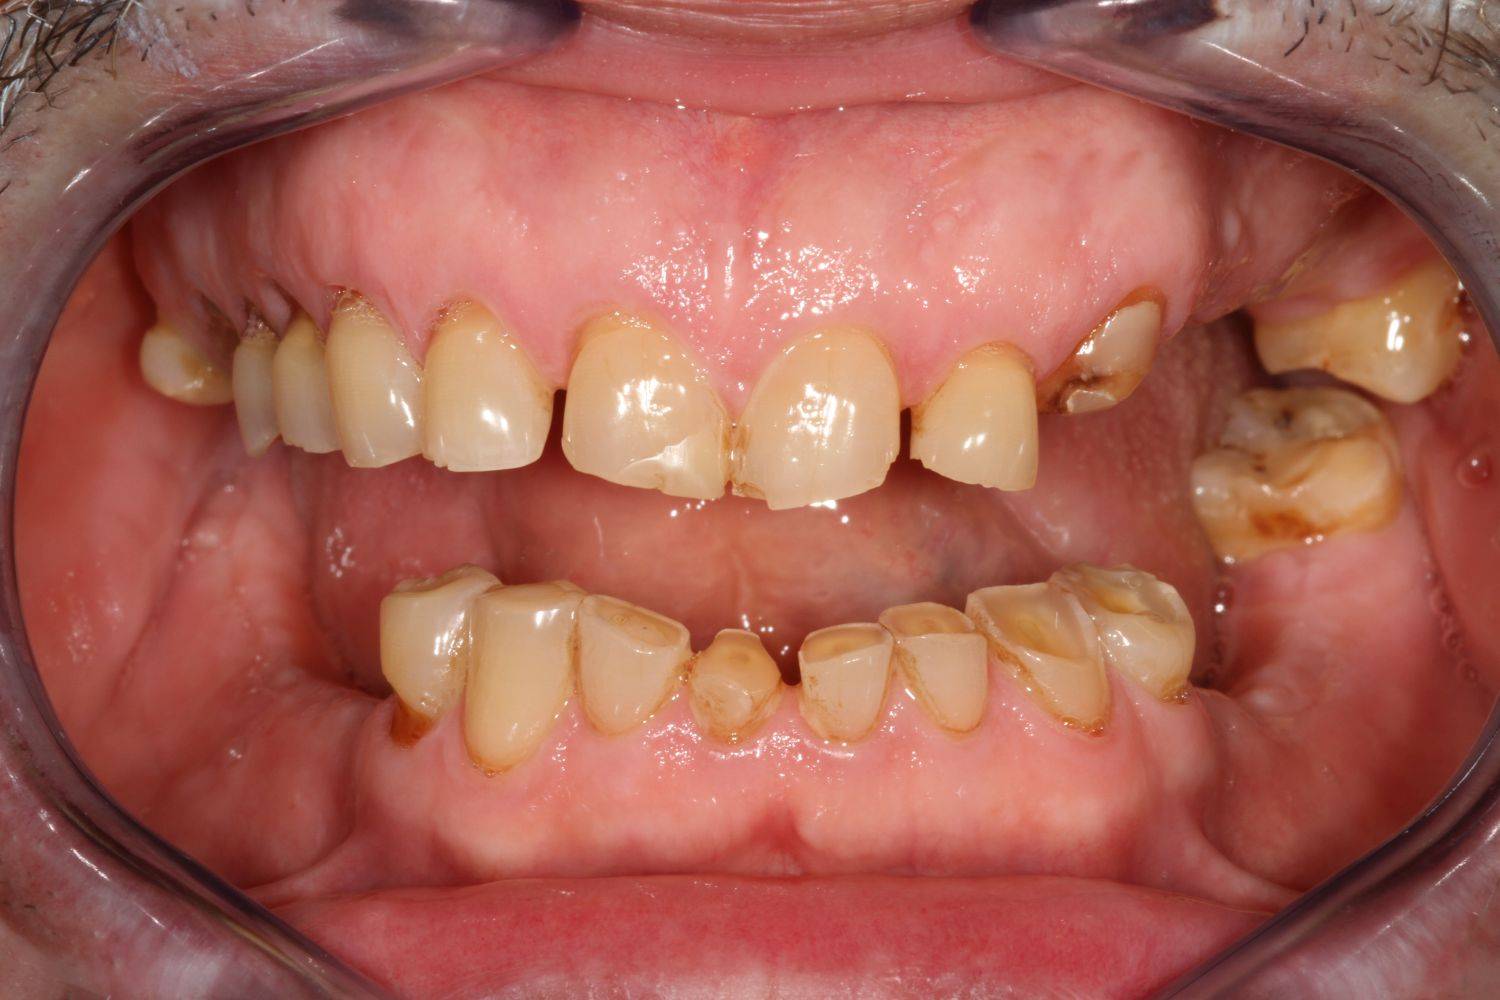

10. eset

Savas kémhatású anyagok, mint például a szénsavas üdítők túlzott használata is a fogak zománcrétegének nagyfokú károsodását okozhatják. 35 éves férfi páciensnek készítettünk a frontfogaira Zirkon koronákat, a rágófogaira pedig fémkerámia szóló koronákat. 28 koronával állítottuk helyre a fogazatot.